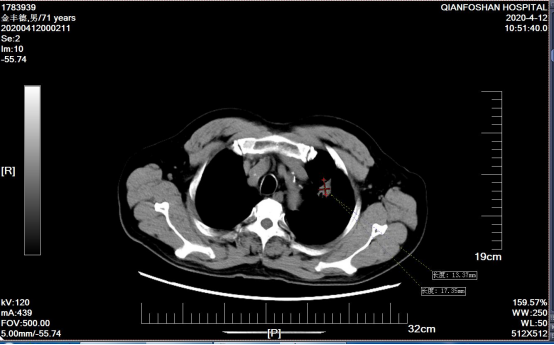

患者氩氦刀治疗结合正规化疗,复查肿瘤持续缩小

经过再次病理检查,李老伯患的确是肺鳞状上皮细胞癌,所以氩氦刀治疗后仍需定期复查,并进行正规化疗。根据刘元水的意见,李老伯每3-4个月回来复查,调整治疗方案,期间可以按照治疗方案在当地医院进行治疗。就像一个约定,此后4年,李老伯风雨无阻,定期从商河赶到山一大一附院复诊。肿瘤微创科医生魏有国介绍说,“患者左肺肿瘤逐渐缩小,病情稳定、治疗过程也很顺利。”四来年,魏有国作为李老伯的主管医师,一直负责他的治疗。“太感激刘主任和魏大夫了,是他们帮我战胜癌症!这里不仅专家好、技术好,能治病,护士也好,服务细致周到,给了我很多帮助和关心。”